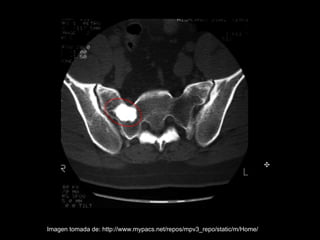

• Las enostosis no es única de los maxilares

puede ocurrir en cualquier parte del esqueleto

como:

– Vértebras

– Huesos ilíaco

– Fémur

– Huesos de la mano, etc

Imagen tomada de: http://www.mypacs.net/repos/mpv3_repo/static/m/Home/